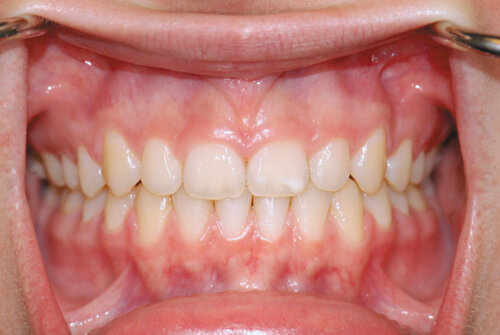

Before

This patient shows severe recession (exposed root surfaces) of the lower front teeth. They lacked the band of thick gum tissue that should be present and instead had only mucosa. This mucosal tissue is thin and mobile (like the inside of your lip), and does not create a protective seal against the tooth.

After

We performed a gum graft utilizing tissue transplanted from the roof of the mouth. The patient achieved a thick, stable long-term result that created a firm protective seal against the tooth to prevent further breakdown.